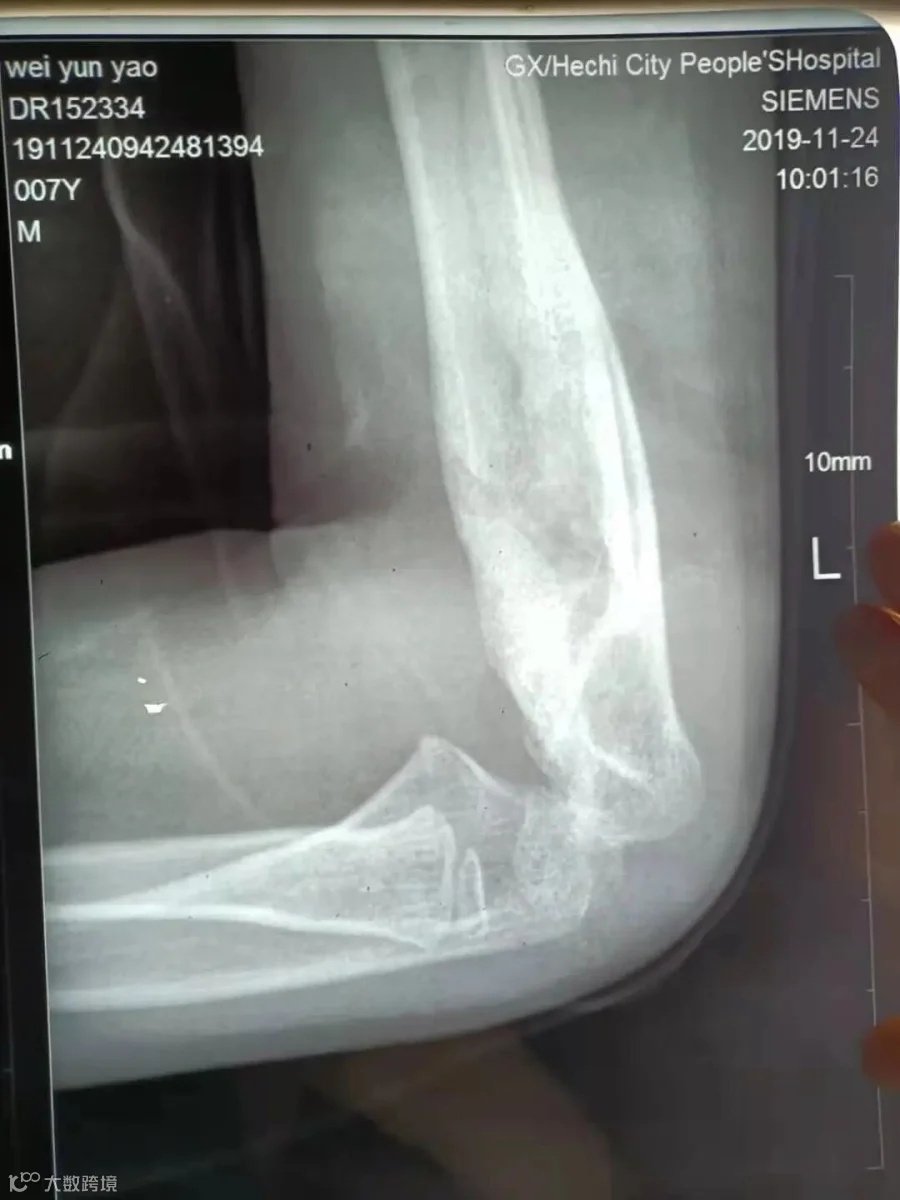

韦韦(化名),6岁8个月

治疗后